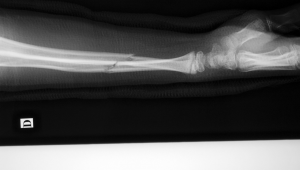

手臂骨折是一种较为常见的骨骼损伤,当遭遇这种情况时,很多热爱运动的人心中都会产生一个疑问:手臂骨折后能踢足球吗?要回答这个问题,我们需要从多个方面进行综合考量。

从受伤恢复的角度来讲,手臂骨折后的恢复是一个循序渐进的过程。骨折初期,骨折部位需要得到充分的固定和休息,以促进骨折的愈合。在这个阶段,任何可能导致手臂受力或震动的动作都是要避免的。踢足球时,身体会处于剧烈运动状态,在奔跑、跳跃、碰撞等过程中,很难保证手臂不会受到意外的碰撞或拉扯,这会对骨折的愈合产生不利影响,甚至可能导致骨折移位,延长恢复时间。即使到了骨折的中期和后期,虽然骨折部位开始有了一定的愈合,但仍然比较脆弱,还需要进行适当的康复训练来恢复手臂的力量和灵活性。在这个时期贸然去踢足球,同样存在再次受伤的风险。只有当骨折完全愈合,经过专业医生的评估和认可,并且手臂的功能已经基本恢复正常,才可以逐渐尝试进行一些低强度的足球活动。